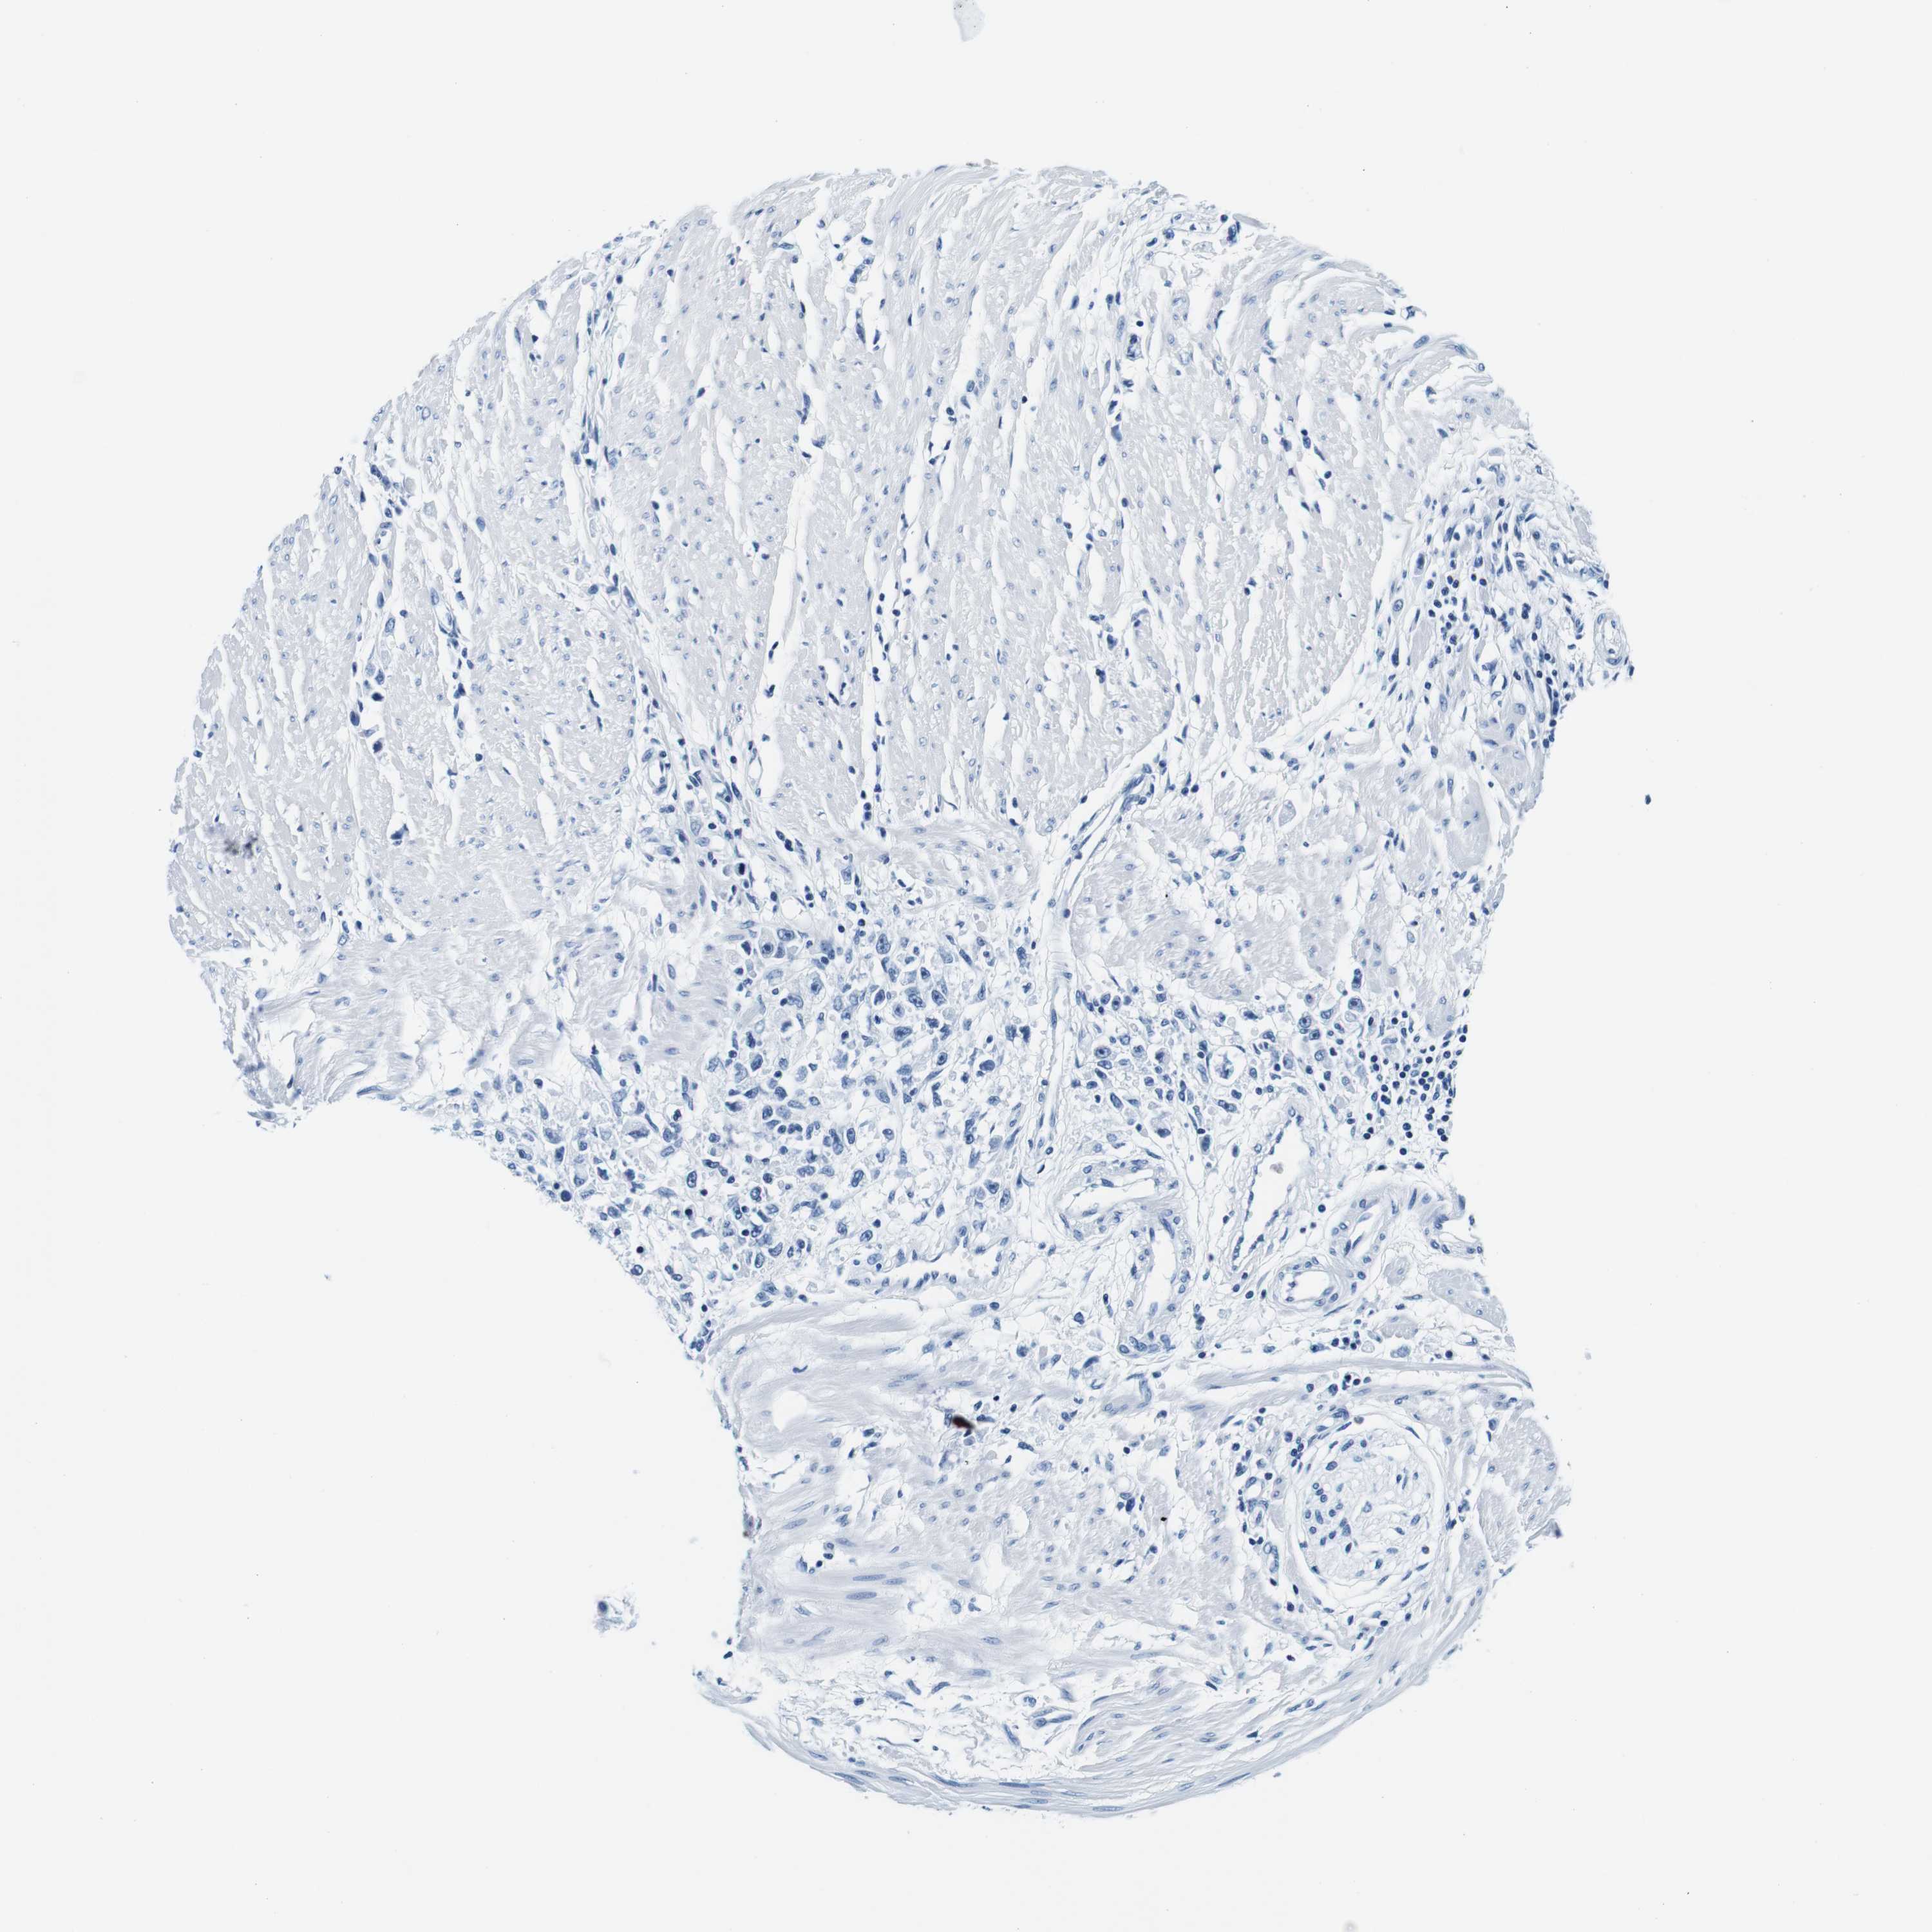

STOMACH CANCER - Protein expressioni

A mouse-over function shows sample information and annotation data. Click on an image to view it in a full screen mode. Samples can be filtered based on level of antibody staining by selecting one or several of the following categories: high, medium, low and not detected. The assay and annotation is described here.

Note that samples used for immunohistochemistry by the Human Protein Atlas do not correspond to samples in the TCGA dataset.

Antibody stainingi

Antibody staining in the annotated cell types in the current human tissue is reported as not detected, low, medium, or high, based on conventional immunohistochemistry profiling in selected tissues. This score is based on the combination of the staining intensity and fraction of stained cells.

Each image is clickable and will lead to virtual microscopy that enables deeper exploration of all samples and also displays staining intensity scores, fraction scores and subcellular localization as well as patient and tissue information for each sample.

Antibody HPA066836

Antibody HPA073774

Antibody CAB015409

Staining

Adenocarcinoma, NOS

Adenocarcinoma, High grade